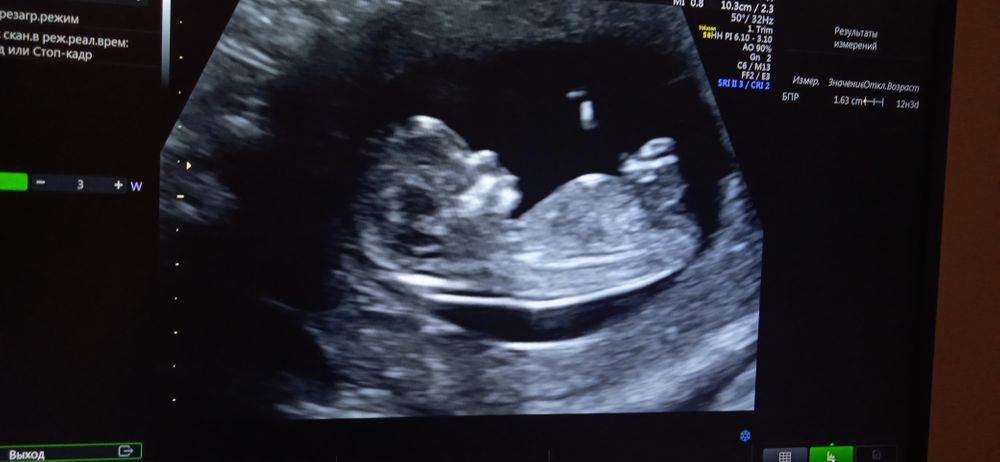

Сделала скрининг первый и думали скажут пол как это и было до этого всегда, но узистка сказала возможно мальчик, но с большой вероятностью ошибки. Может кто по фото поймет?

Ну на первом скрининге реально получить верный результат,проверяла два раза) но у вас тут вроде не видно полового бугорка....

А так, если очень хочется, действительно лучше сдать кровь на пол, точный результат будет